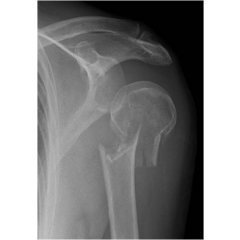

上腕骨頸部骨折

上腕骨近位端骨折は高齢者の特に骨粗鬆症のある患者が転倒した際におこりやすいです。(図1)

症状として、局所の自発痛と運動制限が強く上肢の挙上が制限されます。転位の少ないものは局所の圧痛のみの場合もあるが、2-3日後には皮下出血が肩~胸部、上腕に広がってきます。